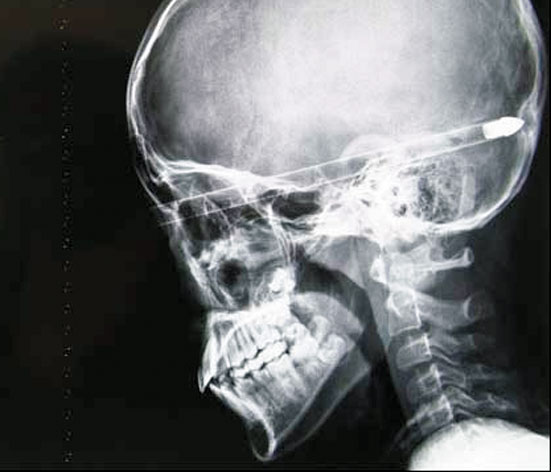

Un elev din China, în vârstă de 11 ani, a supravieţuit, în mod miraculos, după ce o colegă i-a tras din greşeală o săgeată în ochiul drept. Aceasta a străpuns craniul băiatului, însă, din fericire, nu i-a atins creierul. Fetiţa care a tras cu arcul a intrat, de frică, în stare de şoc.

Liu Cheong a fost dus de urgenţă la spital, după ce o colegă cu care se juca a tras din greşeală cu arcul în direcţia sa. Medicii au avut nevoie de patru ore pentru a înlătura săgeata de 40 cm din capul pacientului, care a trecut la doar câţiva milimetri de creier. În timpul operaţiei, chirurgii au scos bucata de fibră din capul copilului pe bucăţi, în aşa fel încât nervii optici sau ţesutul cranian să nu fie foarte afectaţi.

“Dacă săgeata ar fi fost lansată cu mai multă forţă, ar fi ieşit prin spatele capului copilului şi l-ar fi ucis pe loc”, au spus doctorii, precizând că băiatul a supravieţuit în mod miraculos.

Medicii i-au avertizat pe părinţii lui Liu că băiatul lor nu e încă în afara pericolului şi că există riscul apariţiei unor infecţii. În plus, micuţul nu va mai vedea cu ochiul străpuns.